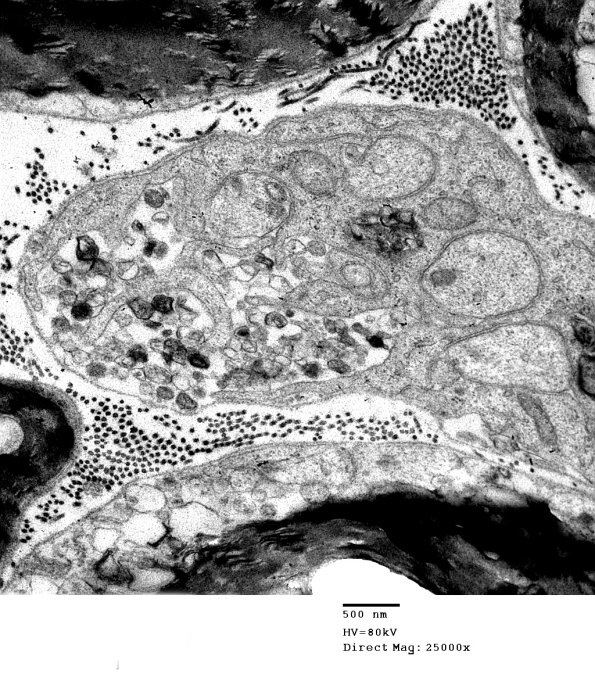

Within a relatively short time the organelles are metabolized and form dark dense aggregates